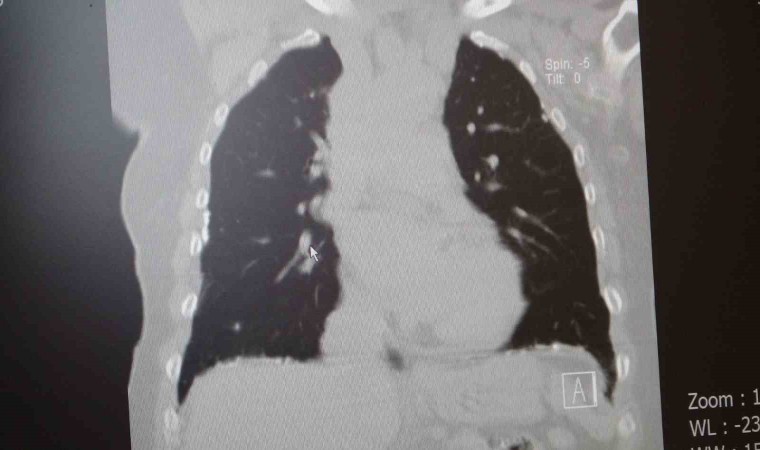

Prof. Dr. Sait Karakurt, "Biliyorsunuz savaş bölgeleri yıkım olan bölgeler. Binaların yıkımı ile birlikte oluşan toz ve parçacıklarla insanlar karşı karşıya kalıyor. bunlar da vücuda zarar verebilir. Bu tozlar içerisinde bir de asbest var. Asbest dikiş iğnesi gibi sivri bir maddedir. Nefes yoluyla akciğere çekildiği zaman adeta oraya batıyor ve vücut bunu uzaklaştıramıyor. Asbeste maruz kalanların 5 kat daha fazla akciğer kanserine yakalandığını biliyoruz. Savaş bölgesinde bulunanlar için mutlaka bulabiliyorsa N95 veya N99 maske takmaları gerekir. Ve yine bölgede patlamalar sonucu oluşan şok dalgaları insan vücudundan geçerken enerjiye bağlı olarak vücuda zarar veriyor. Akciğerde kanama, yırtılma ve ödem meydana getirebiliyor. Bu da zamanla solunum yetmezliğine giden problemler oluşturabiliyor. O bölgelerde yangın da fazla oluyor. yanmaya bağlı partikül ve parçacıklar akciğerlere girip en uç noktasına kadar ulaşıp oradan da vücuda geçme ihtimali olabiliyor. Yangın sırasında dumana maruz kalmak da sorun oluşturuyor. Bir başka sorun da hastalarda var olan hastalıkların artmasıdır. Örneğin astım hastasının yangınlar sonrası karşılaştığı duman ve tozlardan sonra hastalığı alevlenebilir veya çok ciddi boyutlara ulaşabilir. Ya da hiç astımı olmayan bir kişinin aileden gelen astım genetiği vardır, bu yoğun mağduriyet sonrası ilk defa kendisini orada gösterebilir. Patlayıcılar içerisinde bulunan bir takım kimyasallar vücuda zarar verebilir. Fosfor atmosfere girdiği zaman su buharı ile birleşip fosforik asit haline dönebilir. Bu ağırdır ve aşağıya doğru çöker. Yeryüzünde çukur gibi yerlerde daha çok gözükebilir. Deriye temas etmesi halinde yaralar meydana getirir. Nefes yoluyla akciğere çekilmesi aynı yaraların akciğerde de oluşmasına sebebiyet verir. Korunma yöntemi olarak yapacak çok bir şey yok fakat maske takılabilir" dedi.